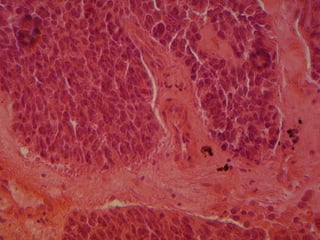

NEOPLASIA CARACTERISTICAS MICROSCOPICAS DE LAS CELULAS MALIGNAS. AUMENTO TAMAÑO NUCLEO (N/C) PLEOMORFISMO NUCLEAR. MITOSIS ATIPICAS CROMATINA GRUMOSA (MEMBRANA CELULAR  ENGROSADA) d)  PERDIDA DE LA ADHESIVIDAD.

NEOPLASIA CARACTERISTICAS MICROSCOPICASDE LAS CELULAS MALIGNAS. AUMENTO TAMAÑO NUCLEO (N/C) PLEOMORFISMO NUCLEAR. MITOSIS ATIPICAS CROMATINA GRUMOSA (MEMBRANA CELULAR ENGROSADA) d) PERDIDA DE LA ADHESIVIDAD.